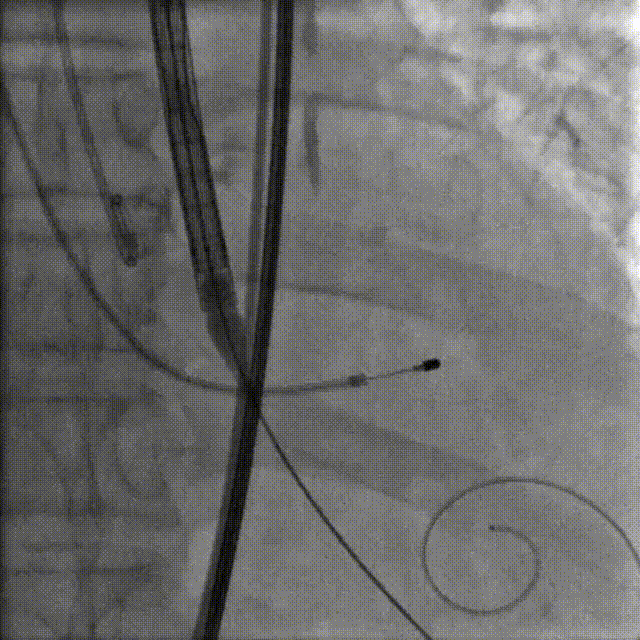

主动脉根部造影

20mm球囊预扩后瓣膜开始定位

工作位造影:左右窦侧瓣架偏深

回收后重新调整释放

工作位造影:位置理想

瓣膜逐个缓慢脱钩

23mm球囊后扩改善形态

最终造影:位置理想,形态良好,无漏